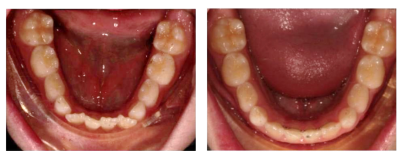

1、牙弓发育问题→可预测扩弓,尤其是传统矫治器难以完成的下颌扩弓

2、替牙期间隙管理→支持恒牙萌出:精确预留空间,使牙齿萌出到矫治器预留空间中